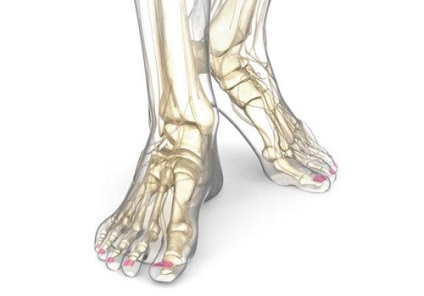

Komputertomográfia (CT) a láb az úgynevezett réteg képek a csont és porc struktúrák a disztális alsó végtag.

A komputertomográfia a láb lehetővé teszi, hogy részletes képet a szerkezet az alsó végtag

Stop - az alsó része a lábát, és elvégzünk egy támogató funkcióját egy rugó, amely lehetőséget biztosít az emberi mozgás, és stabilitását statikus helyzetben.

A láb három körzet:

- Első - ujjai álló phalanxán (két - egy nagy, három - az összes többi).

- Közel - lábközép, térnek, mint egy rajongó minden lépésben, egyre nagyobb a felfekvő felület; megáll, miközben bővül átmérőjű, „lapított”, amely nevét adta ezeket a csontokat.

- Hátsó - lábtő csontok, amelyek közül a legnagyobb sarokcsont támogatást nyújt a láb, hogy egy „talapzaton” a láb csontjai.

A szerkezetek a láb magában ujjak, tarsus és lábközépcsontot

Csak egy 26 láb csontjai, amelyek kapcsolatban vannak egymással ízületek, ínszalagok és izmok. Minden lépésnél, a láb úgy érzi, egy terhelés egyenlő a súlya a test, így az ízületek és szalagok a láb gyakran befolyásolja a gyulladásos vagy degeneratív folyamatok. Szükség van annak vizsgálatára.